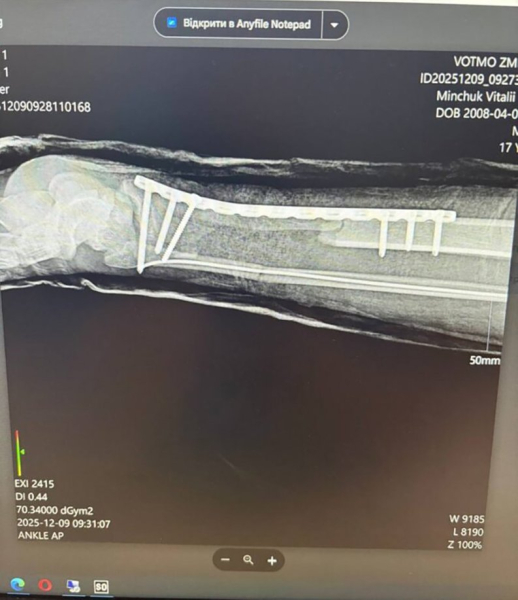

Хірурги Волинської обласної дитячої клінічної лікарні врятували ногу 16-річному Віталію Мінчуку з Камінь‑Каширського району після ДТП 30 листопада: під час зіткнення мотоцикла з автомобілем хлопець зазнав майже повної ампутації лівої гомілки.

Коли пацієнта доставили до лікарні, нога трималася лише на шкірі. Було пошкоджено кістки, м’язи, сухожилки та обидві артерії стопи, причому з моменту травми до госпіталізації пройшло понад 4,5 години й кінцівка залишалася без кровопостачання.

До операції залучили судинних хірургів Степана Курача та Сергія Пісачука; також виконали фіксацію кісток. Наразі стан Віталія стабільний: кровообіг у нозі відновлено, він рухає пальцями, у стопі збереглася чутливість. Попереду тривале лікування та реабілітація.